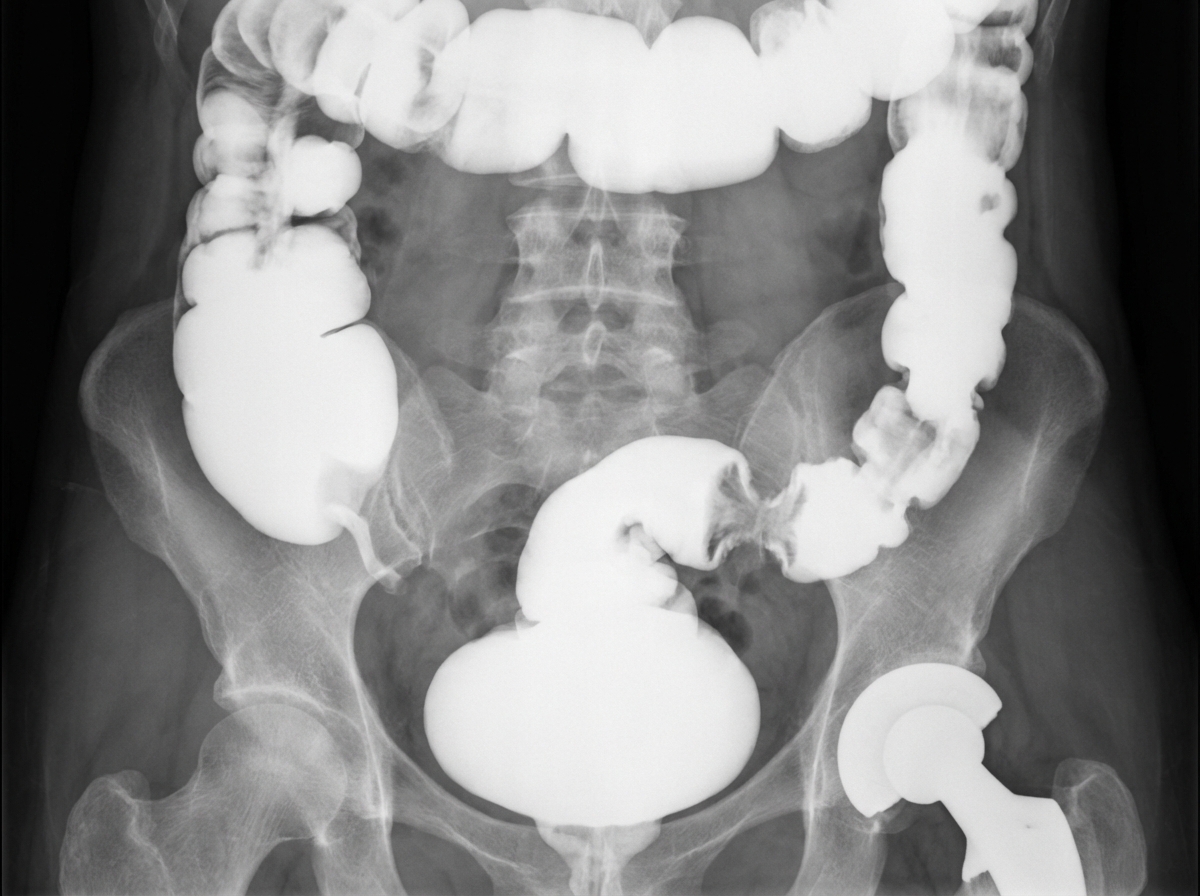

What is the most likely underlying diagnosis in this 82-year-old patient with diabetes mellitus who had undergone a total hip replacement 10 years previously?

Explanation: ***Colon cancer*** - In an **82-year-old diabetic patient**, colon cancer is highly likely given the age demographics and potential **apple-core lesion** or **colonic mass** on imaging studies. - **Metastatic colon cancer** can present with bone lesions near prosthetic joints, and diabetes increases cancer risk through chronic inflammation and immune dysfunction. *Hypogammaglobulinemia* - This **immunodeficiency disorder** typically presents with recurrent infections rather than structural abnormalities on imaging. - Would not cause the characteristic **mass lesions** or **apple-core appearance** seen in gastrointestinal malignancies. *Hypophosphatasia* - A rare **genetic metabolic disorder** affecting bone mineralization, typically diagnosed in childhood or early adulthood. - Would show **osteomalacia** and **rickets-like changes**, not focal mass lesions characteristic of malignancy in elderly patients. *Osteosarcoma* - Primarily affects **children and adolescents** with peak incidence in the second decade of life. - In elderly patients, osteosarcoma is extremely rare and would typically arise from **Paget's disease** or post-radiation, not associated with diabetes or hip prostheses.